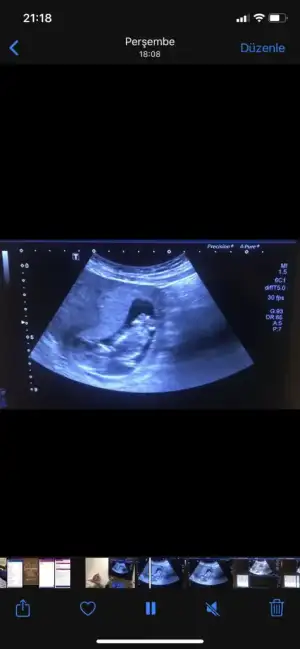

Canlarım ciğerlerimmm nolur vanada yorum yapın çatlicam. Doktor yorum yapmadı. 23. Haftamdayım. Sizce cinsiyet neeeeeee